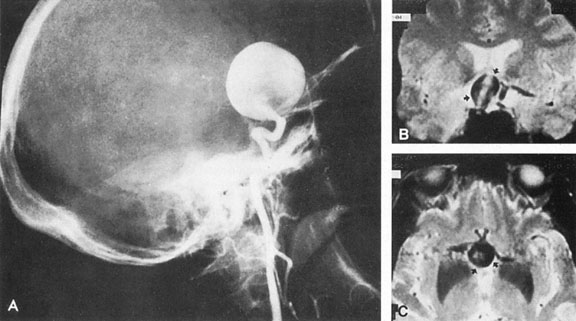

Vertebrobasilar System

Tortuous or redundant basilar arteries are not uncommon in the older age group. Occasionally, gross dilation or ectasia develops so that the basilar artery acts as a mass in the posterior fossa. This phenomenon produces signs of low-pressure hydrocephalus, cranial nerve palsies, and long tract and sensory signs and may even simulate a cerebellopontine angle tumor or tumor at the foramen magnum.58 It is possible to diagnose such lesions with CT59 or MRI60 but angiography is definitive (Fig. 6). The association of insidious multiple cranial nerve palsies and long tract signs referable to a brainstem level, in an elderly patient with evidence of atherosclerosis, should make fusiform basilar artery dilation a diagnostic consideration.

Fig. 6. Fusiform basilar dilation. A: Lateral projection vertebral arteriogram showing a widened basilar artery (arrow) projecting beyond level of dorsum sellae. B: Anteroposterior projection showing a widened and tortuous basilar artery.

As opposed to saccular basilar aneurysms, fusiform aneurysms tend to occur in the older age group (older than 60 years) and are found predominately in men.2,36 They are commonly associated with hypertension and atherosclerotic cardiovascular disease, and a notable association with abdominal aortic aneurysms also exists.